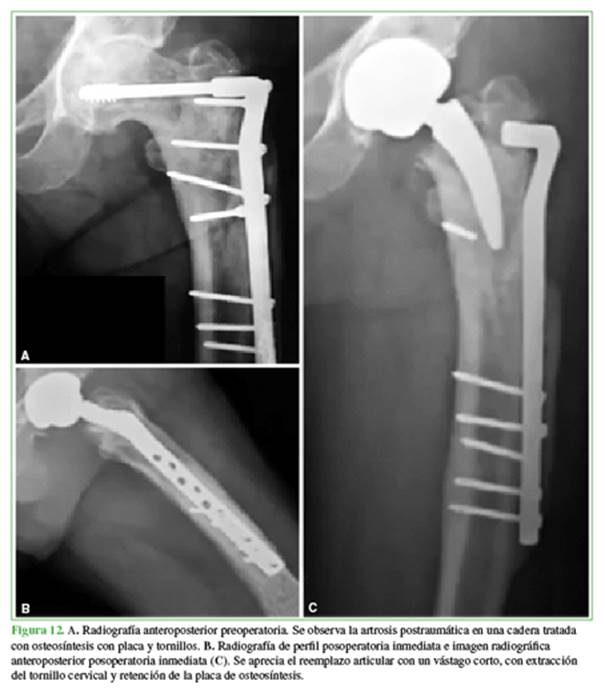

Las deformidades del fémur proximal pueden ocurrir en cualquier nivel. Asimismo, aumentan la dificultad técnica y presentan un elevado riesgo de complicaciones intraoperatorias, como fracturas o perforación cortical, sobre todo cuando existen elementos de osteosíntesis previos de larga data (Figura 12).

El tratamiento del paciente con una deformidad femoral proximal requiere criterio. Los esfuerzos para restituir la anatomía son imperativos, ya que las deformidades residuales no corregidas pueden tener consecuencias biomecánicas adversas. Hemos observado a lo largo de nuestra experiencia con vástagos cortos que dichos implantes evidencian ventajas en los casos con deformidades del fémur proximal, pueden evitar osteotomías femorales concomitantes o bien por tener la capacidad de insertarse evitando la extracción de implantes previos en forma total o parcial.45,77,78 Adicionalmente, pueden compensar deformidades extrarticulares a nivel diafisario (más distales).